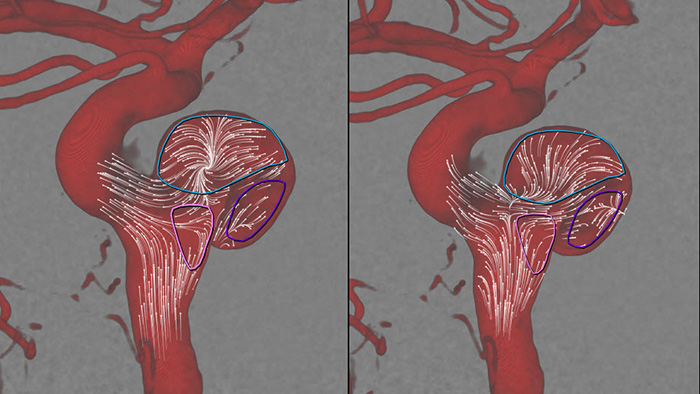

Being able to immediately assess the impact of flow diverters on blood flow is crucial during treatment. AneurysmFlow converts information from a SmartCT Angio acquisition and 2D DSA flow sequences into quantitative flow values. These values are used to visualize and quantify blood flow patterns before and after flow diverter deployment in cerebral aneurysms.

AneurysmFlow helps to visualize and quantify blood flow patterns in the parent vessel and aneurysm sac to obtain key information that can assist deployment of flow diverters and other embolization devices.

AneurysmFlow evaluates changes in blood flow in the aneurysm, by calculating the change in Mean Aneurysm Flow Amplitude (MAFA ratio) before and after flow diverter placement.